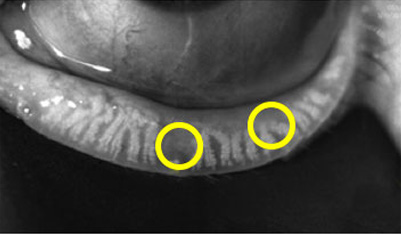

탈락하거나 퇴화한 마이봄(샘)선

염증이 생겨 딱딱하게 굳은 기름샘

정상 마이봄(샘)선

깨끗하고 맑은 기름샘